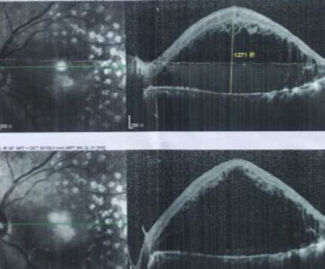

肿、肿、肿…,现在它的海拔上升到1271µm,怎么样?可以和珠穆朗玛峰媲美吧,是的,它很美,但是你的视力则会急剧下降,平面以下或许就是一个眼前指数或手动,怎么办呢?

也许以前我们没办法治疗,可是现在有了抗VEGF药物“雷珠单抗、康柏西普、Ozurdex”,它是黄斑水肿的克星,给予玻璃体腔注射次日就会有效果,我们的"珠穆朗玛峰-黄斑水肿"就会逐渐降低到海平面一下,又会还给我们一个美丽的黄斑中心凹,眼前依然是清新明亮的世界。

经过抗VEGF治疗,“黄斑水肿”已经完全消退了,眼底恢复了正常,眼底照像如同一轮明月,黄斑中心凹犹如大海一样为我们展现出一幅曼妙的“海上生明月”,重新拣回我们的视力,神奇吗?是的,现代医学的发展已经有了化时代的变化,新的药物层出不穷,黄斑疾病已经不是不治之症了。